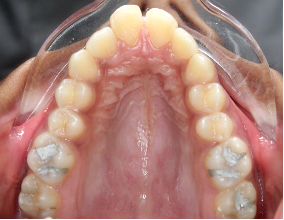

Fig.3 Bone- tooth anchored design: Only 2 anterior TADs and support of molars